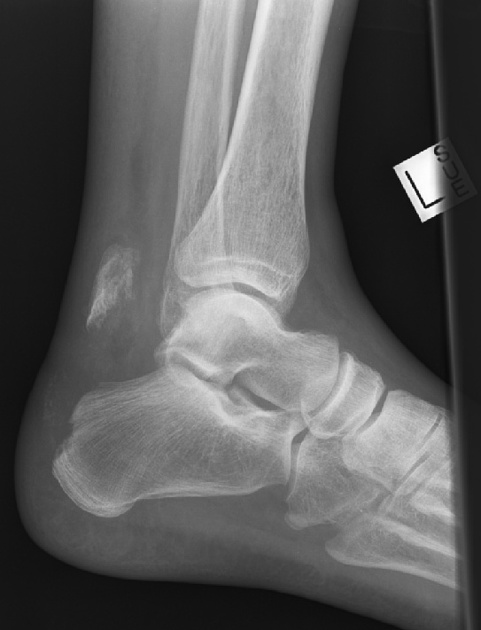

Avulsion fracture - Definition

A ligament or tendon pulls away from its attachment on the bone, and a fragment of bone breaks off with it

Avulsion fracture - Cause

A muscle contraction or stretch that is stronger than the force that holds the tendon or ligament to the bone